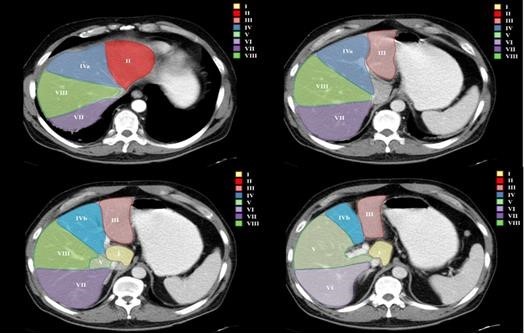

Hallazgos imagenológicos

El diagnóstico se realiza mediante ecografía (Modo B y Doppler) y se confirma la extensión y la presencia de factores asociados mediante TC con CTE y RM con CTE EV.

Hallazgos ecográficos

Se observa material ecogénico dentro de la luz portal o de algunas de sus ramas. En el caso de los trombos malignos, es difícil su diagnóstico mediante este método (tanto en el modo B como en el estudio Doppler). Debemos sospecharlo ante una lesión hepática asociada o un trombo que presenta señal Doppler en su interior con un flujo que puede presentar onda arterial.

El método inicial es la ecografía (Modo B y Doppler), dada su alta disponibilidad y bajo costo, aunque tiene la desventaja de ser operador dependiente.

El Gold Estándar es la TC con contraste EV.